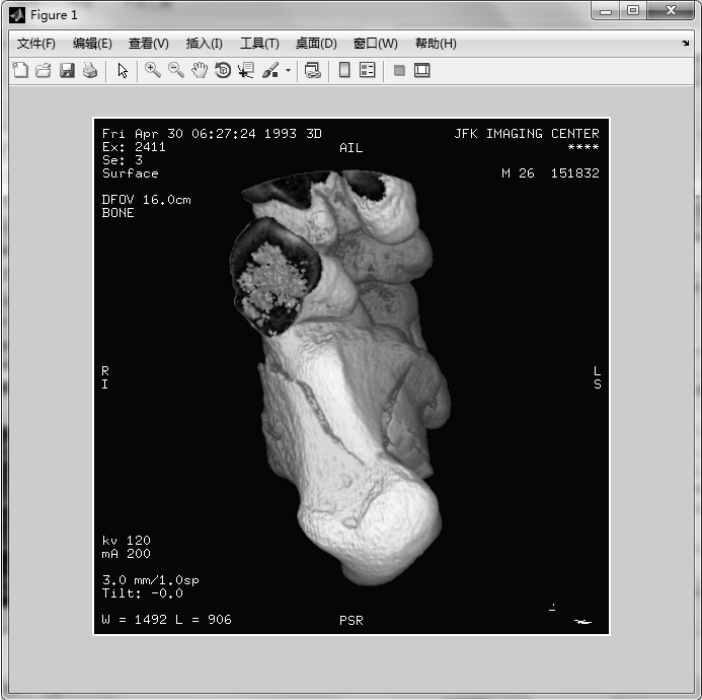

【实例2】 从DICOM元数据结构中读取图像数据。

图1.43 从DICOM元数据结构中读取图像数据